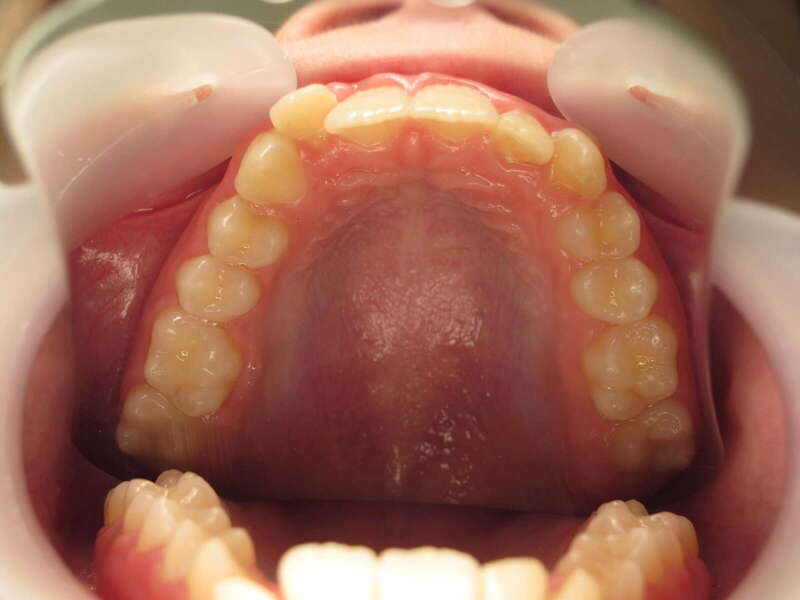

Cas n°1 traité par aligneurs (interception) - enfant

Ce cas d’interception chez un enfant de 8 ans démontre l'efficacité des aligneurs pour corriger des troubles fonctionnels précoces. Le diagnostic présentait des inversions d'articulé provoquant une déviation de la mandibule vers la gauche et un décalage des milieux.

Grâce à une coopération exemplaire et un traitement totalement indolore, l'expansion de l'arcade a permis de recentrer la mâchoire. Cette intervention a littéralement remis la croissance sur les rails, neutralisant le risque d'asymétrie faciale squelettique.

• Correction fonctionnelle : Recentrage immédiat de la mandibule et des milieux inter-incisifs.

• Prévention : Création d'un environnement favorable pour les dents définitives à venir.

• Bien-être : Approche douce respectant le confort de l'enfant.

C'est une étape fondamentale qui simplifie l'avenir orthodontique du patient tout en garantissant un développement facial harmonieux.